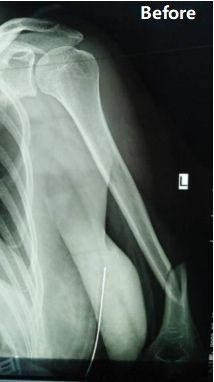

Fall übersicht: Bei einer 48-jährigen Patientin wurde eine Fraktur des mittleren bis distalen Drittels des linken Humerus schachts diagnosti ziert (AO-Klassifikation: Typ B1).